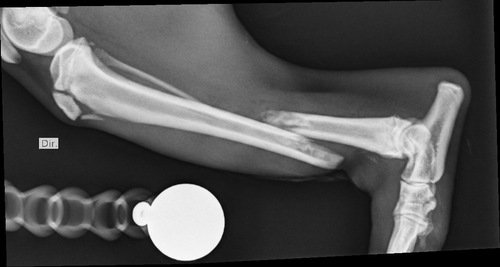

Tatu fugiu e foi atropelado, o motorista fugiu e não prestou socorro, ele teve 3 fraturas e terá que a realizar 3 cirurgias, fora exames e a internação na clínica  ver tudo

Tatu fugiu e foi atropelado, o motorista fugiu e não prestou socorro, ele teve 3 fraturas e terá que a realizar 3 cirurgias, fora exames e a internação na clínica